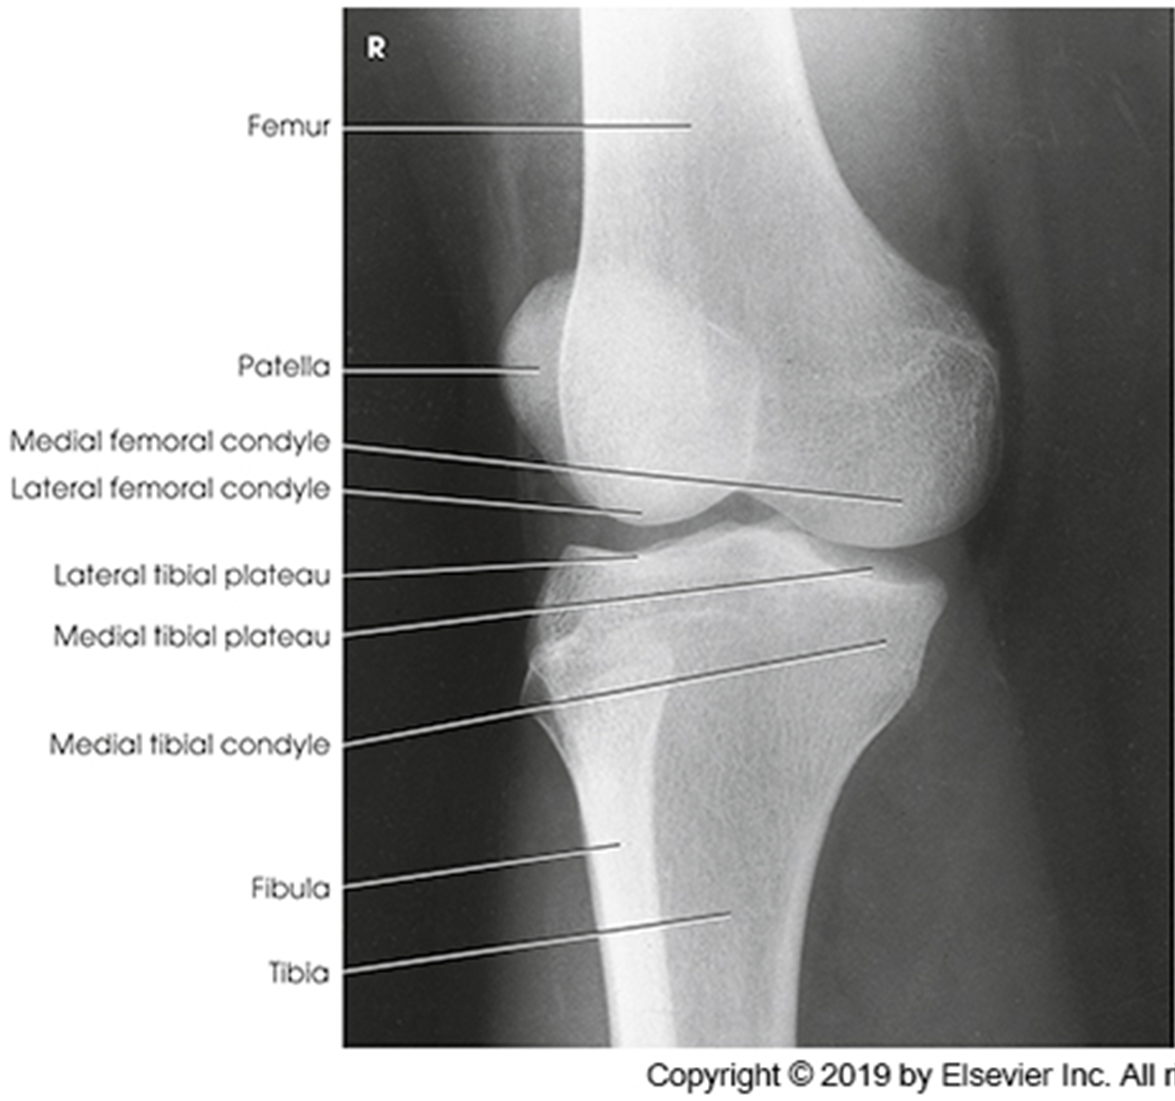

Anatomy of the knee

Trauma and Non Trauma AP Knee

•Evidence of proper collimation and the presence of a side marker placed clear of the anatomy of interest

•Knee fully extended if patient’s condition permits

•Entire knee without rotation

•Femoral condyles symmetric and tibia intercondylar eminence centered

•Slight superimposition of the fibular head if the tibia is normal

•Patella completely superimposed on the femur

•Open femorotibial joint space, with interspaces of equal width on both sides if the knee is normal

•Bony trabecular detail and surrounding soft tissues